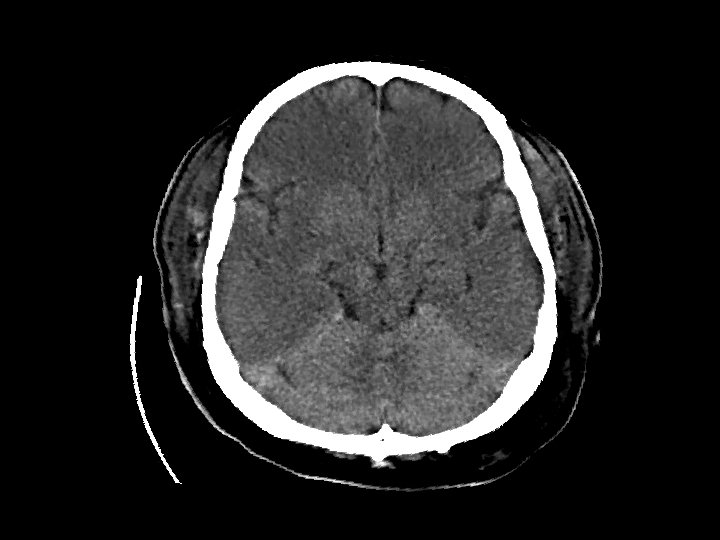

Anoxic Brain Injury Findings Hypodense cerebral hemispheres with

Anoxic Brain Injury • Findings: – Hypodense cerebral hemispheres with effacement of cortical gyri – Relative sparing of cerrebellum • Due to global insult: – Profound hypotension – Carbon monoxide poisoning • MRI findings: – Dense basal ganglia